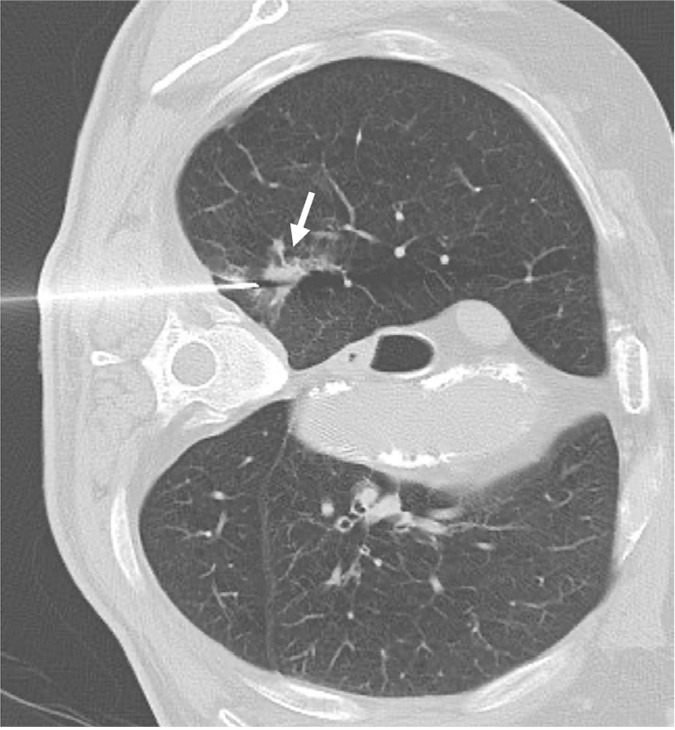

Purpose: Percutaneous biopsy has demonstrated high accuracy in diagnosis of lung nodules, but the technique is not innocuous and a yield decrease in lesions smaller than 20 mm has been reported. We carried out a prospective study to evaluate and compare the complications and efficacy of percutaneous core needle biopsy (CNB) of solitary solid lung nodules, which were performed with two types of automatic guns.

Methods: 330 consecutive CT-guided CNB were included. Tru-cut or end-cut 18G devices were used alternatively. Nodules were categorized by their size: ≤10 mm, 11-20 mm and >20 mm. Incidence of complications such as pneumothorax or hemoptysis and factors influencing them (nodule size and depth within lung parenchyma) were evaluated. Diagnostic accuracy of CNB achieved in the three groups of nodules regarding the two different needles were calculated and statistically evaluated and compared.

Results: We performed 68 CNB in nodules ≤10 mm, 130 in 11-20 mm and 132 in >20 mm. Pneumothorax appeared in 24.2% of them, but only 5.7% required drainage. Hemoptysis was developed in 9.4% and abundant hemoptysis with hypoxemia was observed in only 4.2% of patients. Regarding appearance of complications between the two needle types, no significant differences were found. A higher risk of hemoptysis was observed in nodules ≤10 mm (OR = 3.87; 95% CI = 1.24-12.06, P = 0.019) and in those located deeper in pulmonary parenchyma (OR = 2.21; 95% CI = 1.04-4.69, P = 0.038). End-cut needles reached a diagnostic accuracy of 93.7%, 92.1% and 98.3%, in nodules sized ≤10 mm, 11-20 mm and >20 mm, respectively. Corresponding results for tru-cut were 84.7%, 88.5% and 92.1%. In spite of differences reaching up to 9% in smaller nodules, intra-group results were not significant.

Conclusion: Both needles have similar complications rate. Despite not having observed statistically significant differences between the two types of needles, end-cut devices have demonstrated a higher diagnostic yield in the three groups of nodules and could be a more suitable option especially for CNB of nodules ≤10 mm.